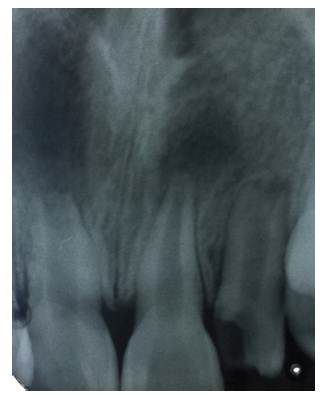

El trauma dentoalveolar (TDA) se define como una lesión de extensión e intensidad variables de origen accidental o intencional; es causado por fuerzas que actúan sobre el órgano dental y los tejidos que le rodean, pudiendo ser observadas o diagnosticadas a simple vista o con la ayuda de la radiografía (foto 1 y 2). Siempre debe ser considerado como una situación de urgencia que debe diagnosticar y tratar rápida y certeramente al odontólogo general integral 1. Sin embargo, su manejo es una fuente constante de dificultades para el clínico, debido a la complejidad del diagnóstico y tratamiento adecuado 2, entendiendo que el pronóstico dependerá de un rápido y adecuado tratamiento 3)-(5.